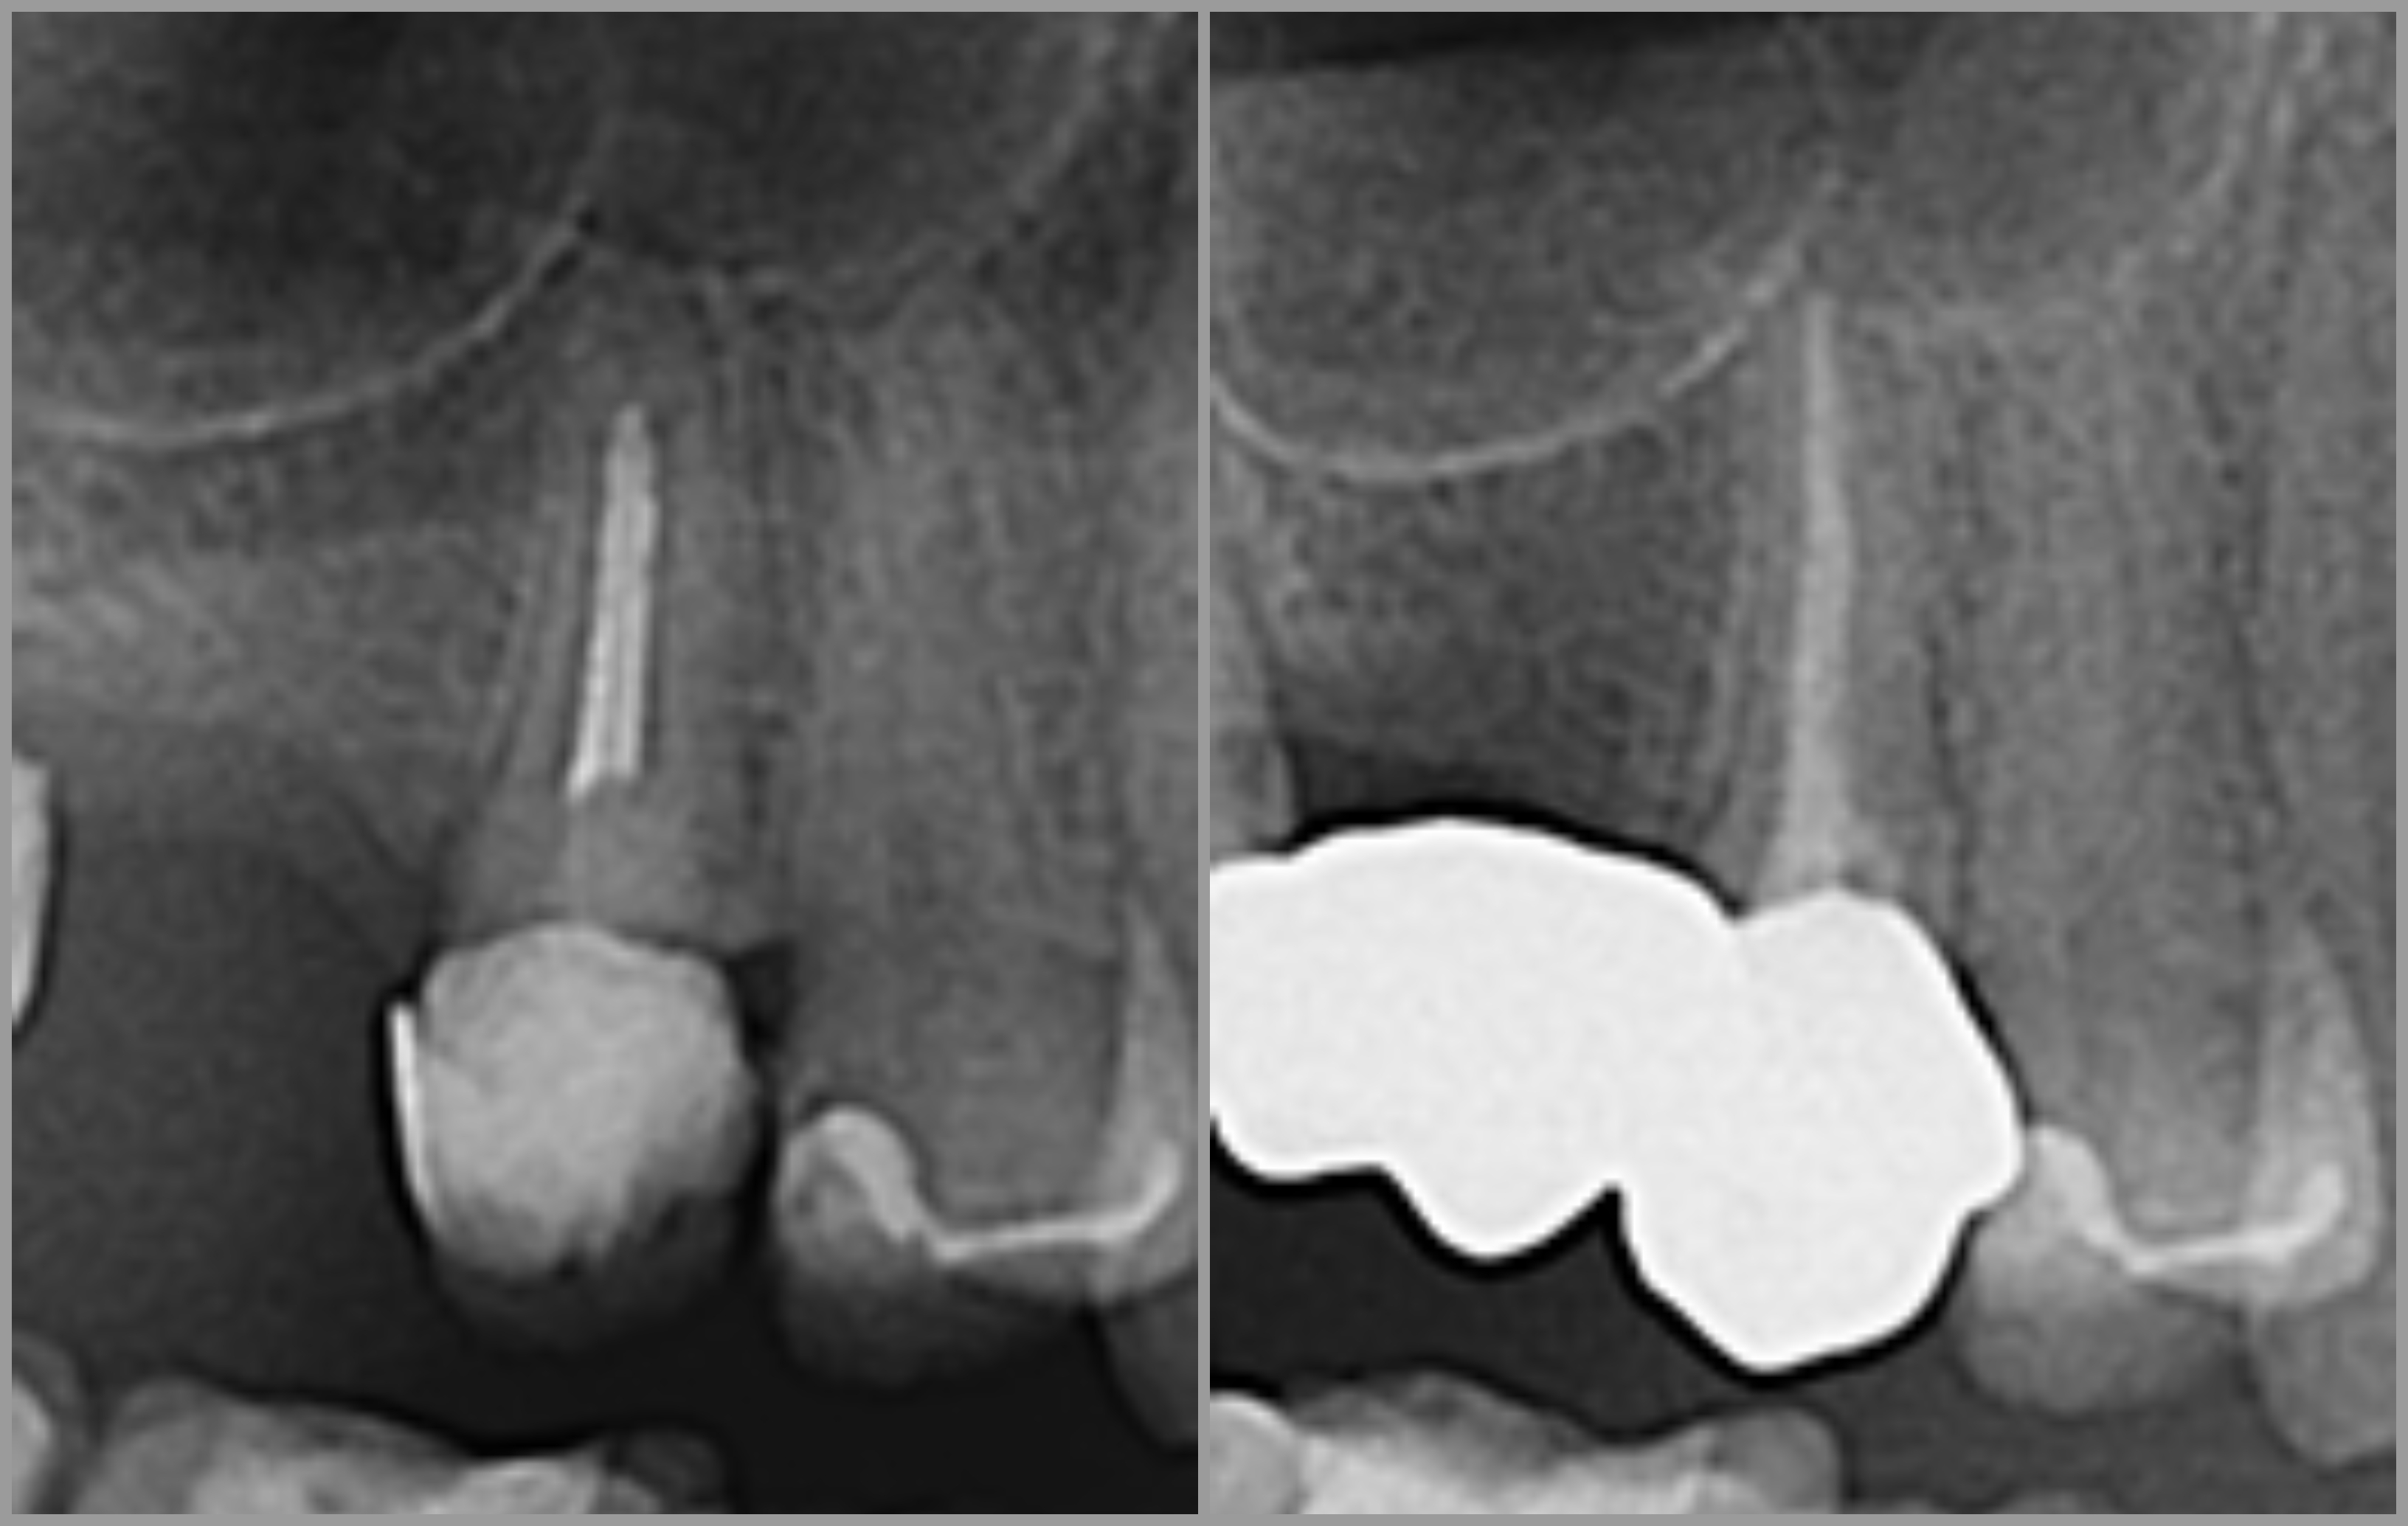

Ako se zub s upalnim procesom ne liječi, dolazi do širenja upale na kost i stvaranja upalnog procesa oko vrha korijena, odnosno dolazi do razvoja granuloma.

Endodontska terapija započinje uklanjanjem karijesom zahvaćenog zubnog tkiva, nakon čega se odstranjuje upaljena zubna pulpa te se kemijski i mehanički čisti zubni kanal radi uklanjanja bakterija i inficiranog dentina.